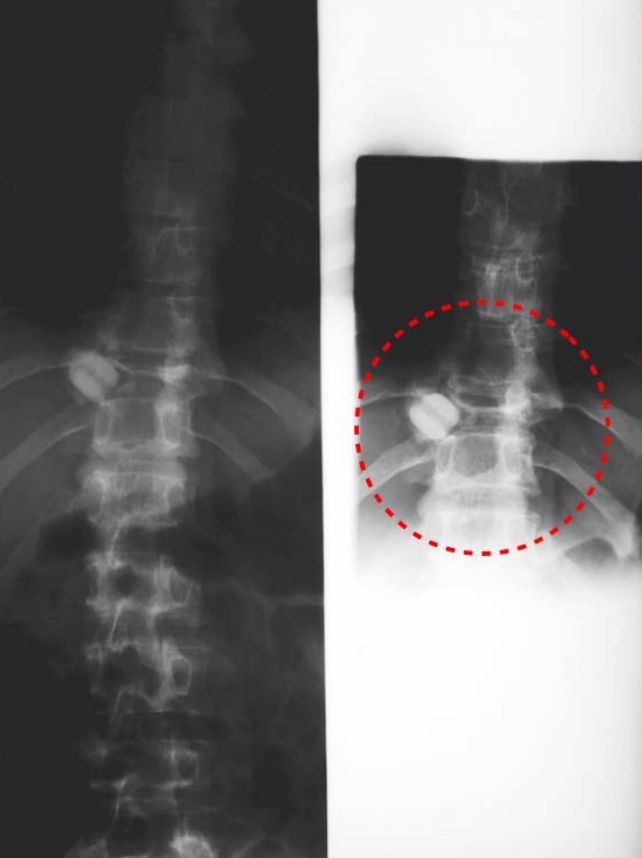

Figure1